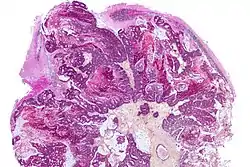

Diagnosis

Brain imaging (neuroimaging such as CT or MRI) is needed to determine the presence of brain metastases.[5] In particular, contrast-enhanced MRI is the best method of diagnosing brain metastases, though detection is primarily done by CT.[9] Biopsy is often recommended to confirm diagnosis.[5]

The diagnosis of brain metastases typically follows a diagnosis of a systemic cancer.[9] Occasionally, brain metastases will be diagnosed concurrently with a primary tumor or before the primary tumor is found.

In brain metastasis due to malignant melanoma, MRI imaging showed high T1 and low T2 intensity due to the deposition of melanin in the brain. In susceptibility weighted imaging (SWI), it usually shows abnormal SWI hypointensity in larger proportion than brain metastasis caused by breast carcinoma.[11]